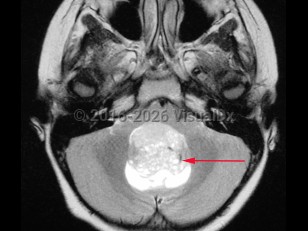

Medulloblastoma in Adult

A medulloblastoma is a malignant primary brain tumor located in the posterior fossa near the fourth ventricle. It is the most common malignant brain tumor in children. One-third of cases present in children aged younger than 3 years. In adults, the tumor usually presents before age 40.

This tumor may spread through the cerebrospinal fluid (CSF) to other parts of the brain and spinal cord. It is an aggressive tumor and recurrence is common. Five-year survival rates are about 60% in all age groups. Patients with medulloblastoma are considered higher risk if they present as infants or at an older age, have metastatic disease, and if their tumors have aggressive histopathology or specific molecular markers.